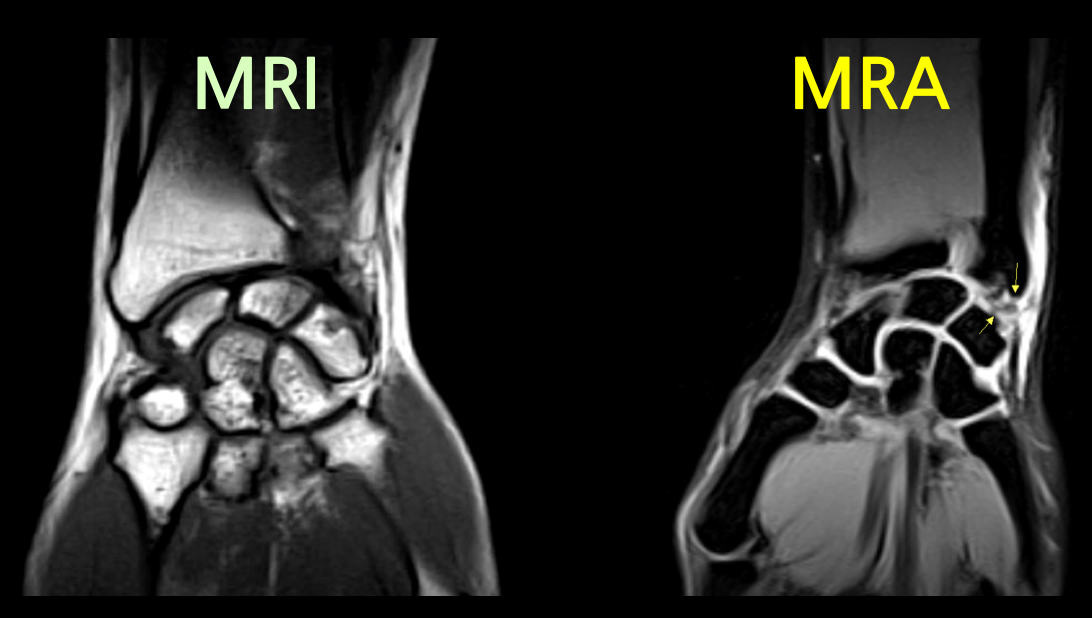

MRA는 MRI와는 다르게 조영제를 사용하며 특히, 같은 부위를 촬영하더라도 조영제 유무에 따라서 촬영된 영상 이미지에 큰 차이가 존재합니다.

작고 좁은 관절에 연부조직을 확인하기 위하여 조영제를 사용하며, 손상여부 및 정도를 확인할 수 있습니다.

정형외과에서 MRA는 어깨, 팔꿈치, 발목과 같은 관절에 적용합니다. 초음파로 확인하기 어려운 관절 전체구조를 확인하고 관절 내 이상소견 및 연부조직 손상여부, 감염등을 확인하는데 큰 도움을 줍니다.

어깨, 팔꿈치, 발목 관절에 조영제를 주입하여 MRI를 촬영하면 조영제가 손상된 틈으로 스며들어 관절 속 미세한 병변까지 진단할 수 있습니다. 이를 관절조영증강 MRI 또는 MRA(Magnetic Resonance Arthrogram)이라고 부릅니다.